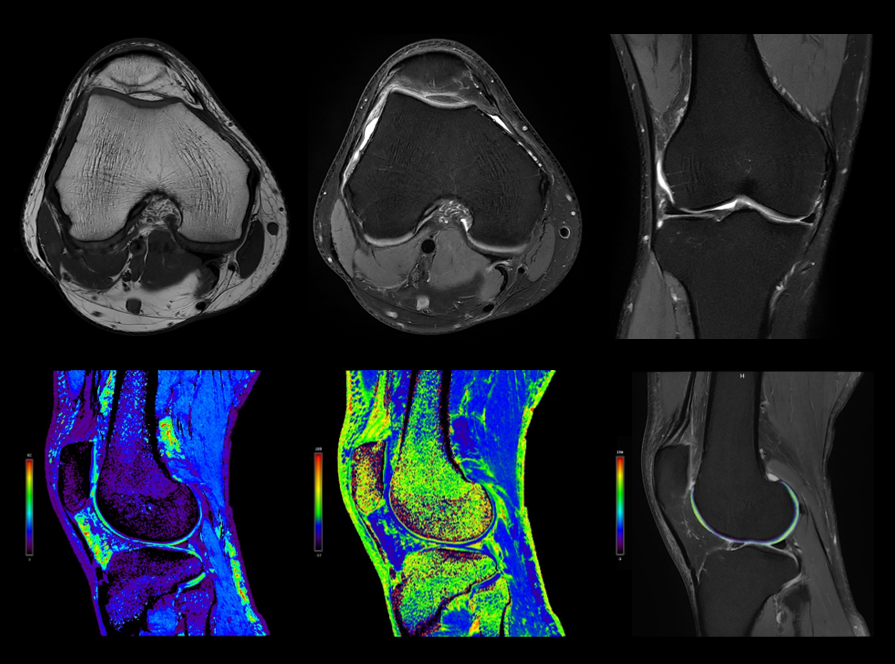

高分辨膝关节成像